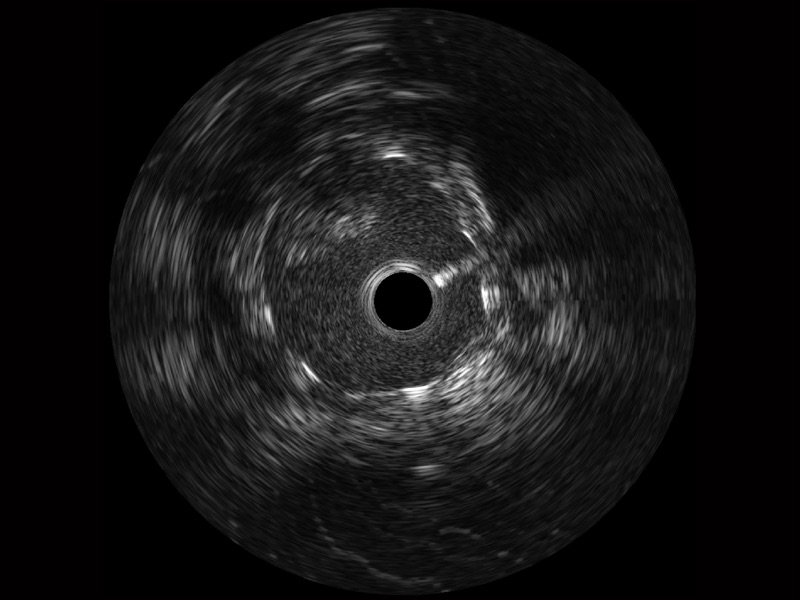

• 百老汇电子游戏官网宽频IVUS图像

对比传统IVUS导管成像,百老汇电子游戏官网宽频IVUS图像的近场支架梁显影更细腻,远场中膜外血管仍清晰可辨,兼顾远中近,兼顾分辨力与穿透深度